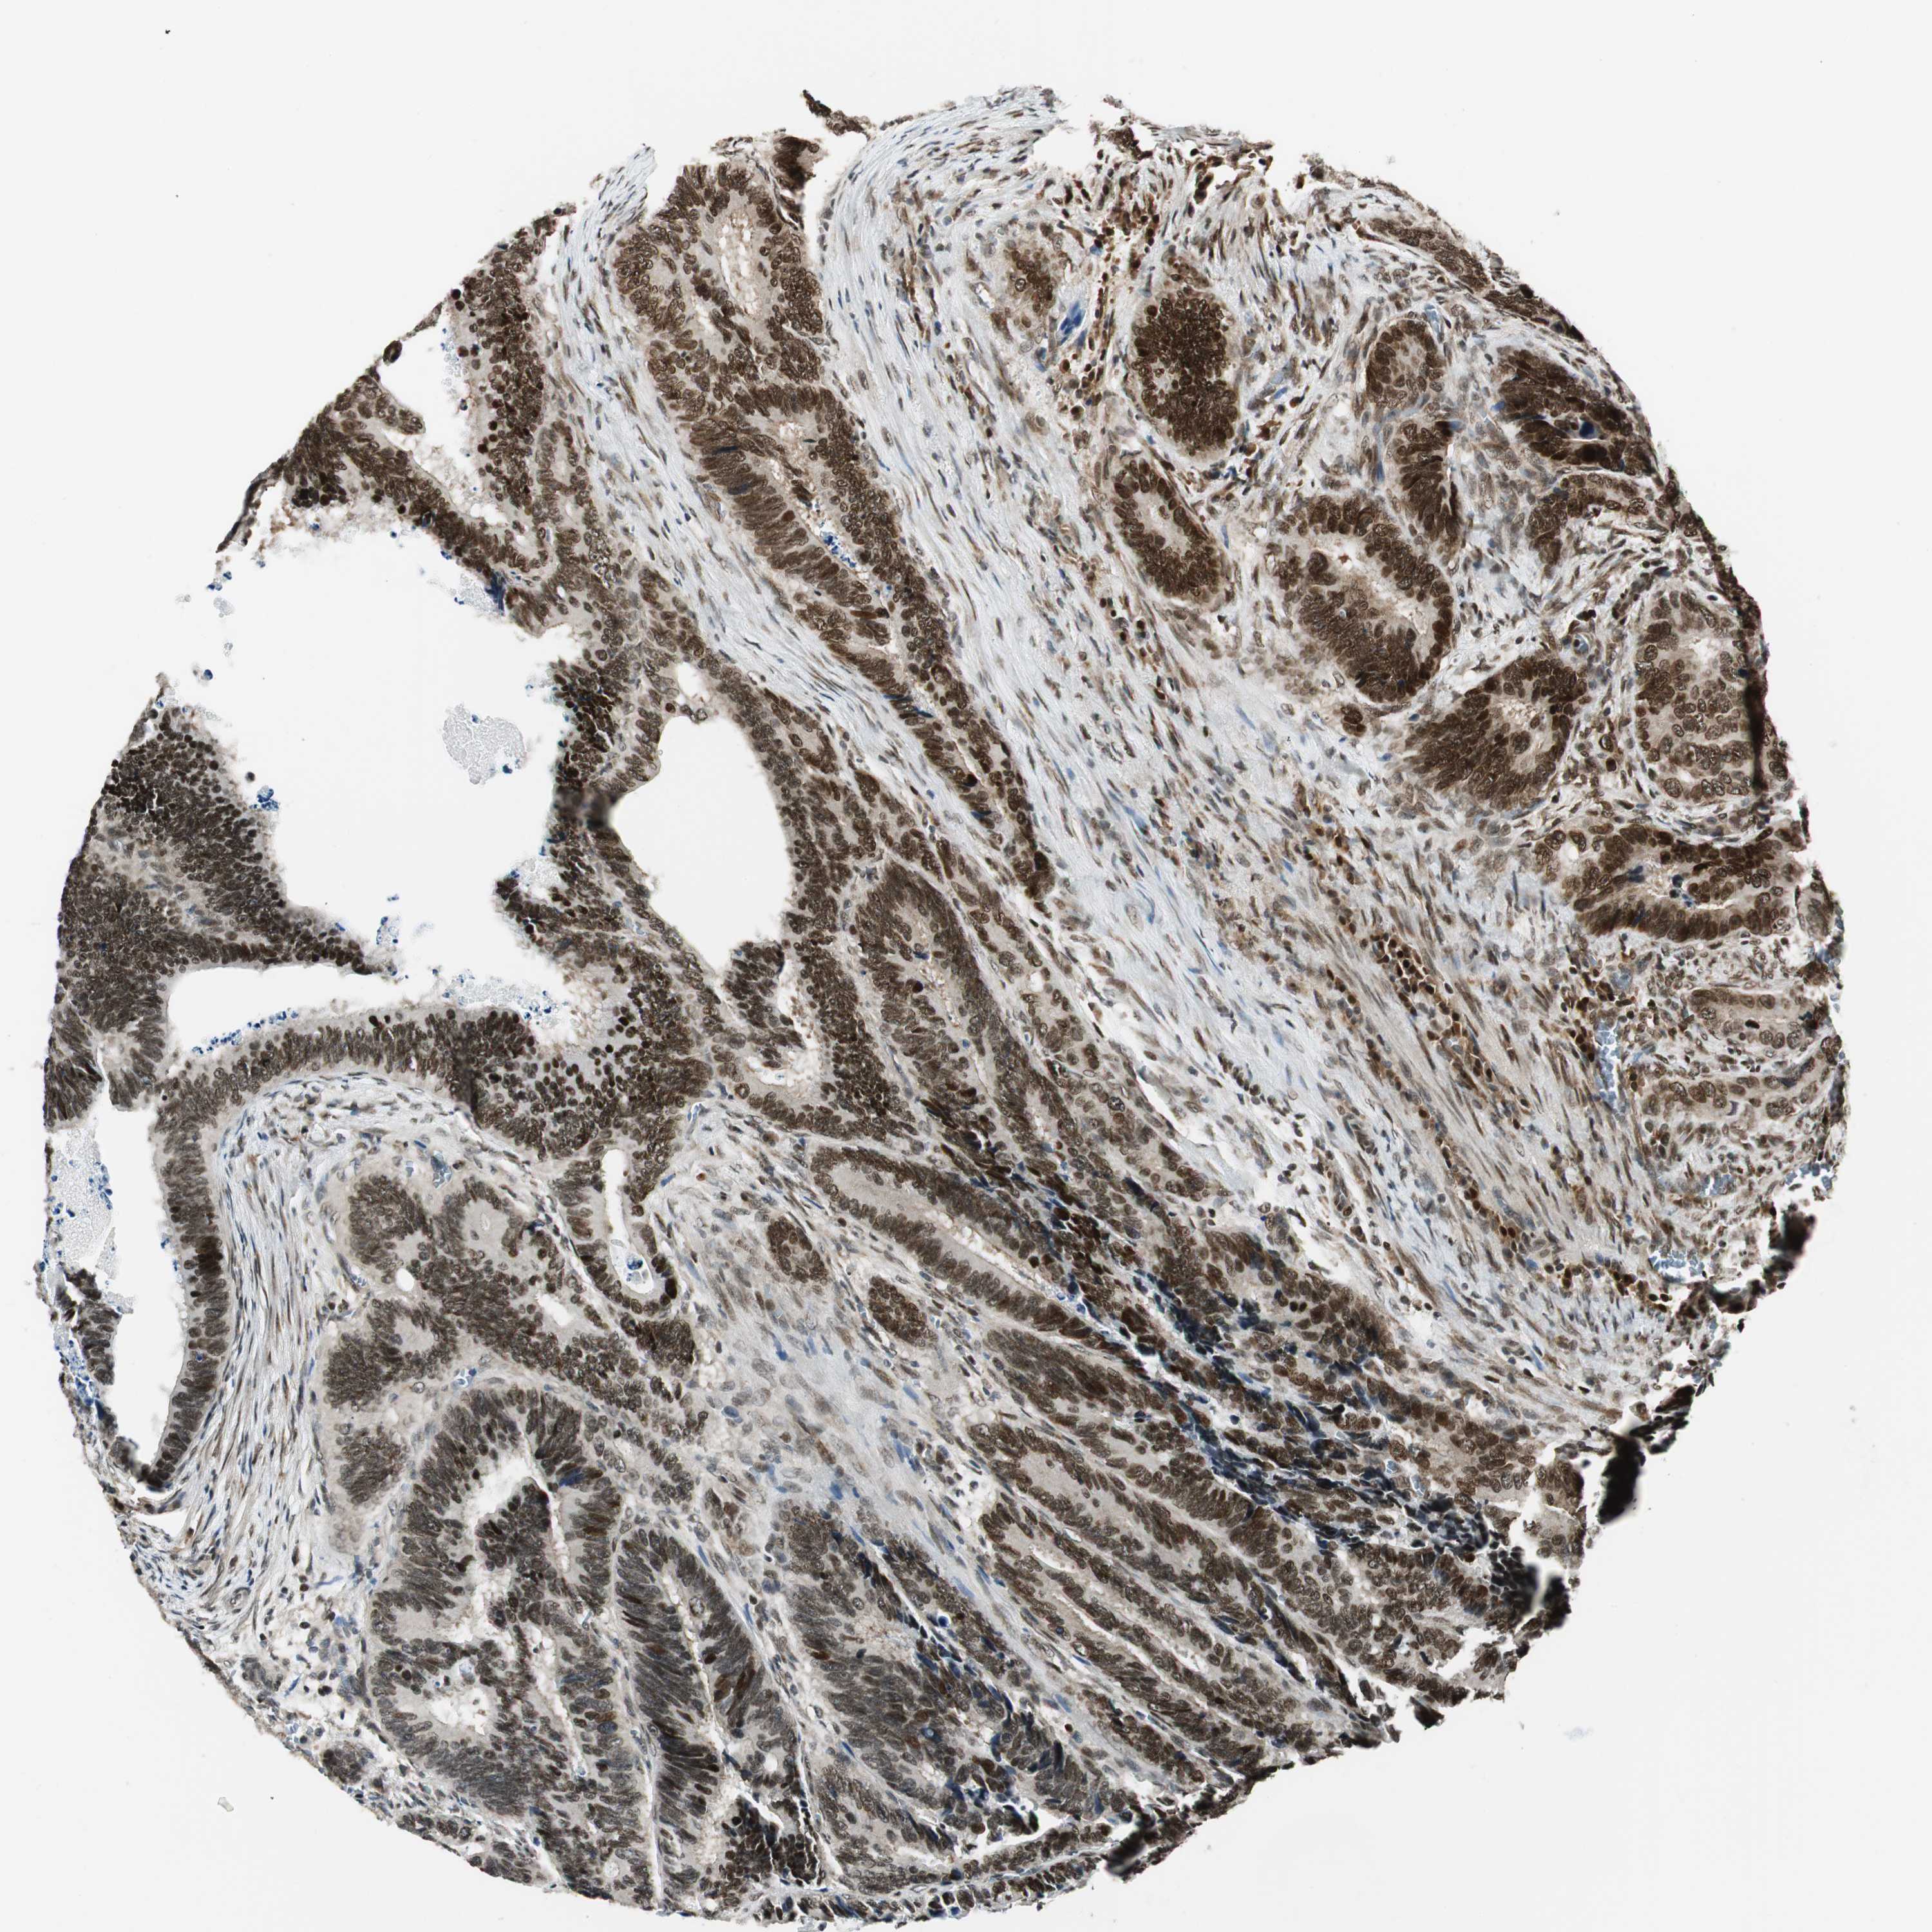

CANCER COLORECTAL CANCER Show tissue menu

Colorectal cancer

Human cancer

Colon adenocarcinoma